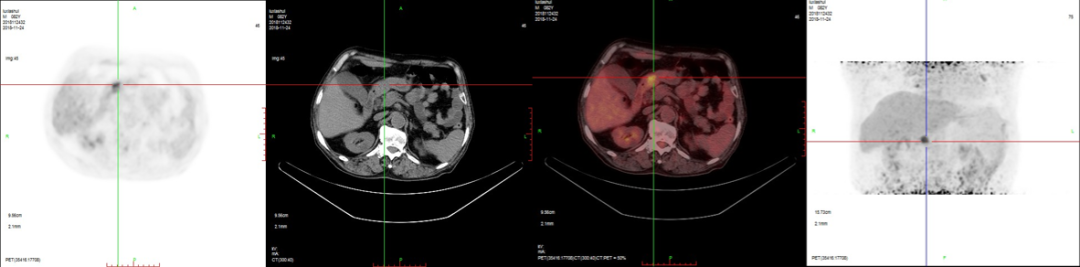

2、肝臟轉(zhuǎn)移。

病例3:男性,72歲。結(jié)腸腺癌術(shù)后3年,右肺鱗癌術(shù)后1年隨訪。